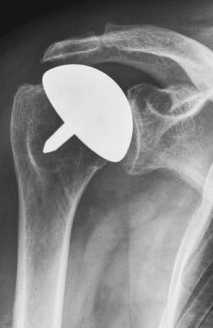

Плечевая гемиартропластика или поверхностное эндопротезирование плечевого сустава. Восстановление поверхности плечевой кости © Wikipedia

Гемиартропластика или поверхностное эндопротезирование плечевого сустава

При поверхностном эндопротезировании плечевого сустава замещается лишь поврежденная хрящевая поверхность плечевой головки. Кость плечевой головки при этом не удаляется. Такая модель протеза применяется в тех случаях, когда стабилизирующие мышцы плечевого сустава (вращающая манжета плеча) не повреждены или повреждены лишь незначительно, а плечевая впадина (гленоид) не имеет признаков износа. Благодаря такому типу протеза плечевой сустав восстанавливается при помощи установки металлической поверхности на плечевую головку на вершине плечевой кости. Хрящ на поверхности суставного углубления (гленоид) остается незатронутым. поверхностное эндопротезирование плечевого сустава позволяет сохранить неповрежденную или неизношенную поверхность сустава.

Одной из основных проблем при поверхностном эндопротезировании плечевого сустава является продолжающийся с течением времени износ поверхности суставного углубления. При преждевременном износе гленоидного компонента могут усиливаться болевые ощущения, а подвижность и несущая способность сустава снижаться.

После гемиартропластики плечевого сустава среднее улучшение амплитуды движения во всех направлениях составляет более 40°. Такой клинический результат схож с результатом после полного эндопротезирования плечевого сустава. Перед проведением поверхностного эндопротезирования специалист по плечевому суставу должен тщательно оценить поверхность суставной впадины и удостовериться в том, что она находится в достаточно хорошем состоянии, позволяющем достичь успешных результатов лечения.

При условии возможности проедения поверхностного эндопротезирования этот метод считается оптимальным методом лечения, поскольку он позволяет сохранить естественную поверхность кости и костное вещество плеча. При этом, если в будущем потребуется повторная операция, ее будет намного проще провести.